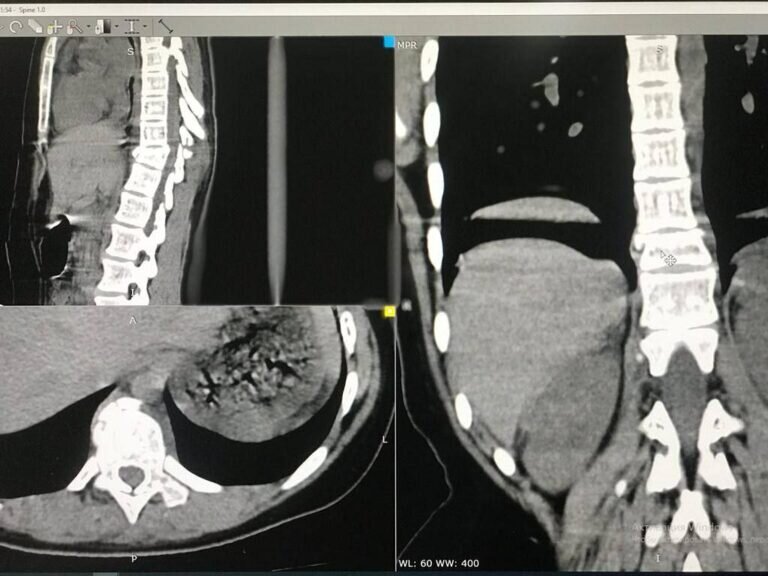

Оренбургские хирурги Дмитрий Казюлин и Иван Четвериков провели уникальную операцию на позвоночнике подростка. Несчастный случай произошел в конце апреля. Подростки катались на качелях, одна из девочек упала с них. При падении она получила перелом позвоночника с деформацией и ушибы внутренних органов. Врачи центральной детской хирургии приняли решение провести операцию и установить специальную фиксирующую конструкцию. Операция длилась около 3-х часов под полным рентген-контролем. Хирурги впервые проводили такую сложную операцию без привлечения специалистов из других медицинских учреждений. 12 мая девочку выписали домой, но прогнозы врачей пока очень осторожные. Фото: https://t.me/odkb56 18+

При падении она получила перелом позвоночника с деформацией и ушибы внутренних органов.

Врачи центральной детской хирургии приняли решение провести операцию и установить специальную фиксирующую конструкцию. Операция длилась около 3-х часов под полным рентген-контролем.